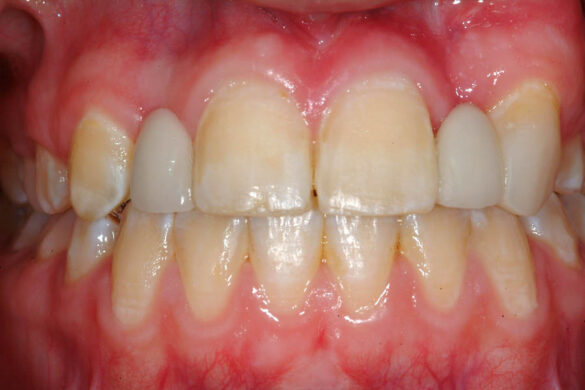

A doua etapă a tratamentului a fost amânată până în aprilie 2006, când pacienta a împlinit vârsta de 11 ani şi 5 luni. În acel moment, fetiţa prezenta erupţie şi dezvoltare radiculară adecvată, astfel că aparatele fixe aplicate acum n-ar fi purtate o perioadă îndelungată. Ocluzia inversă frontală şi angrenajul invers lateral fuseseră corectate; totuşi, exista o diastemă mare, în principal cauzată de lipsa incisivilor laterali superiori (fig.3). În acest moment, radiografia panoramică relevă anodonţia incisivilor laterali maxilari şi a premolarului secund drept mandibular, o anatomie redusă a rădăcinilor incisivilor centrali superiori, incluzia caninului superior stâng şi dezvoltarea întârziată a rădăcinii celui de-al doilea premolar inferior (fig. 4).